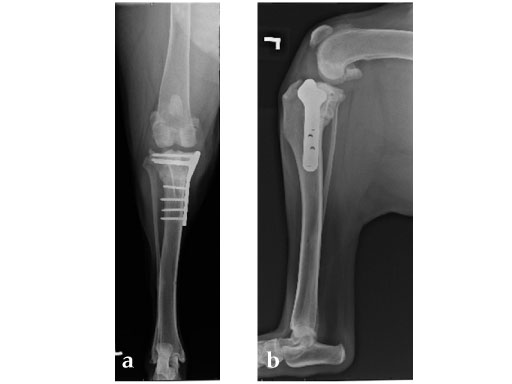

Case 1: Two-year-old Labrador Retriever

2-years-old Labrador Retriever, 30 kg, female. Chronic lameness in both hind limbs, chronic bilateral cranial cruciate ligament tears, with subsequent stifle joint instability and degenerative joint disease. At that time, she was more clinically lame on the left hind limb, and a surgical correction was subsequently performed on this limb. X-rays of the stifle joint revealed the degenerative joint changes and an effusion; the tibial plateau slope was 20. In addition, the x-rays confirmed that there was a slight amount of tibial torsion that also was observed clinically, accounting for a slight internal rotation of the distal limb. Radiographically, this could be assessed by a 4 mm shift of the normal point of intersection of the medial aspect of the calcaneus with the deepest point of the talar sulcus.

The stifle joint was surgically explored. All remaining remnants of the torn cranial cruciate ligament were debrided; in addition, the caudal pole of the medial meniscus was torn/crushed, and a partial meniscectomy of the damaged portion was performed. A TPLO plate 3.5 was applied to stabilize the fracture. The plate was applied in a neutral fashion. Postoperative x-rays revealed a tibial plateau angle of 5, and a correction of the torsion to 0 mm.

Follow-up x-rays at 8 weeks postoperatively revealed that the osteotomy had healed, and the dog was doing very well. The identical procedure was performed on the opposite stifle joint 2 months later. Healing was again obtained 8 weeks postoperative. Presently, the dog is about 1 year postoperatively and functioning very well.